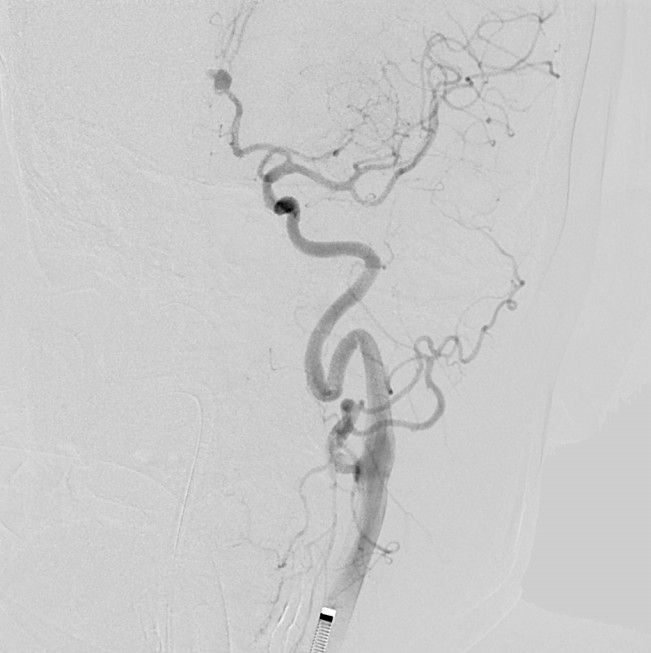

Endovascular Coiling of a Ruptured DACA Aneurysm — A Life-Saving Neuro intervention

A 50-year-old woman presented with a sudden thunderclap headache — a hallmark warning sign of subarachnoid hemorrhage (SAH). With a background of irregular hypertension treatment, MRI confirmed:

Subarachnoid Hemorrhage (Grade 2)

Ruptured saccular aneurysm in the left Anterior communicating artery A2 segment

An emergency endovascular coiling procedure was performed to occlude the ruptured aneurysm — preserving cerebral circulation while preventing rebleed.